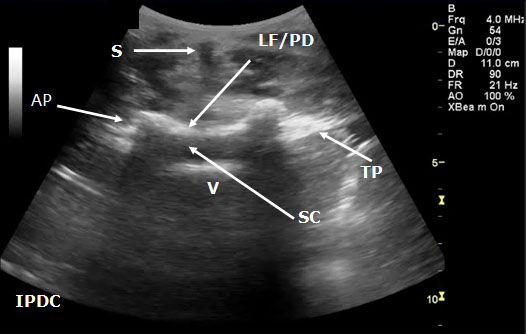

A low-frequency curved array transducer is needed in the lumbar spine region. The 2 views used to visualize the spinal canal and its associated landmarks include the paramedian longitudinal (Figure 14) and transverse (axial) windows (Figure 15). A paramedian longitudinal (sagittal) view is the best window for sagittal scanning that minimizes the acoustic artifact shadowing associated with bony structures.[40][43] The appropriate interspace can be identified in the sagittal view based on counting from the landmark of the sacrum.

In the transverse approach the transducer is placed perpendicular to the long axis of the spine. The window is identified in which shadow of the spinous processes is minimal. Structures that can be visualized with ultrasound include the ligamentum flavum/posterior dura complex, spinous processes, transverse processes, superior articular processes, facet joints, and the posterior border of the vertebral body. In certain cases it is not always possible to distinguish the ligamentum flavum from the posterior dura and the anterior dura from the posterior longitudinal ligament and the vertebral body. Ultrasound has also been utilized as an adjuvant tool in the performance of caudal epidurals (Figure 16).

Figure 15. Transverse sonogram of the lumbar interspace. At times it may be difficult to distinguish the ligamentum flavum from the posterior dura. LF/PD = Ligamentum Flavum/Posterior Dura Complex. SC = Spinal Canal. V = Vertebral Body. S = Shadow of the Spinous Process. T= Transverse Process. AP = Articular Process.